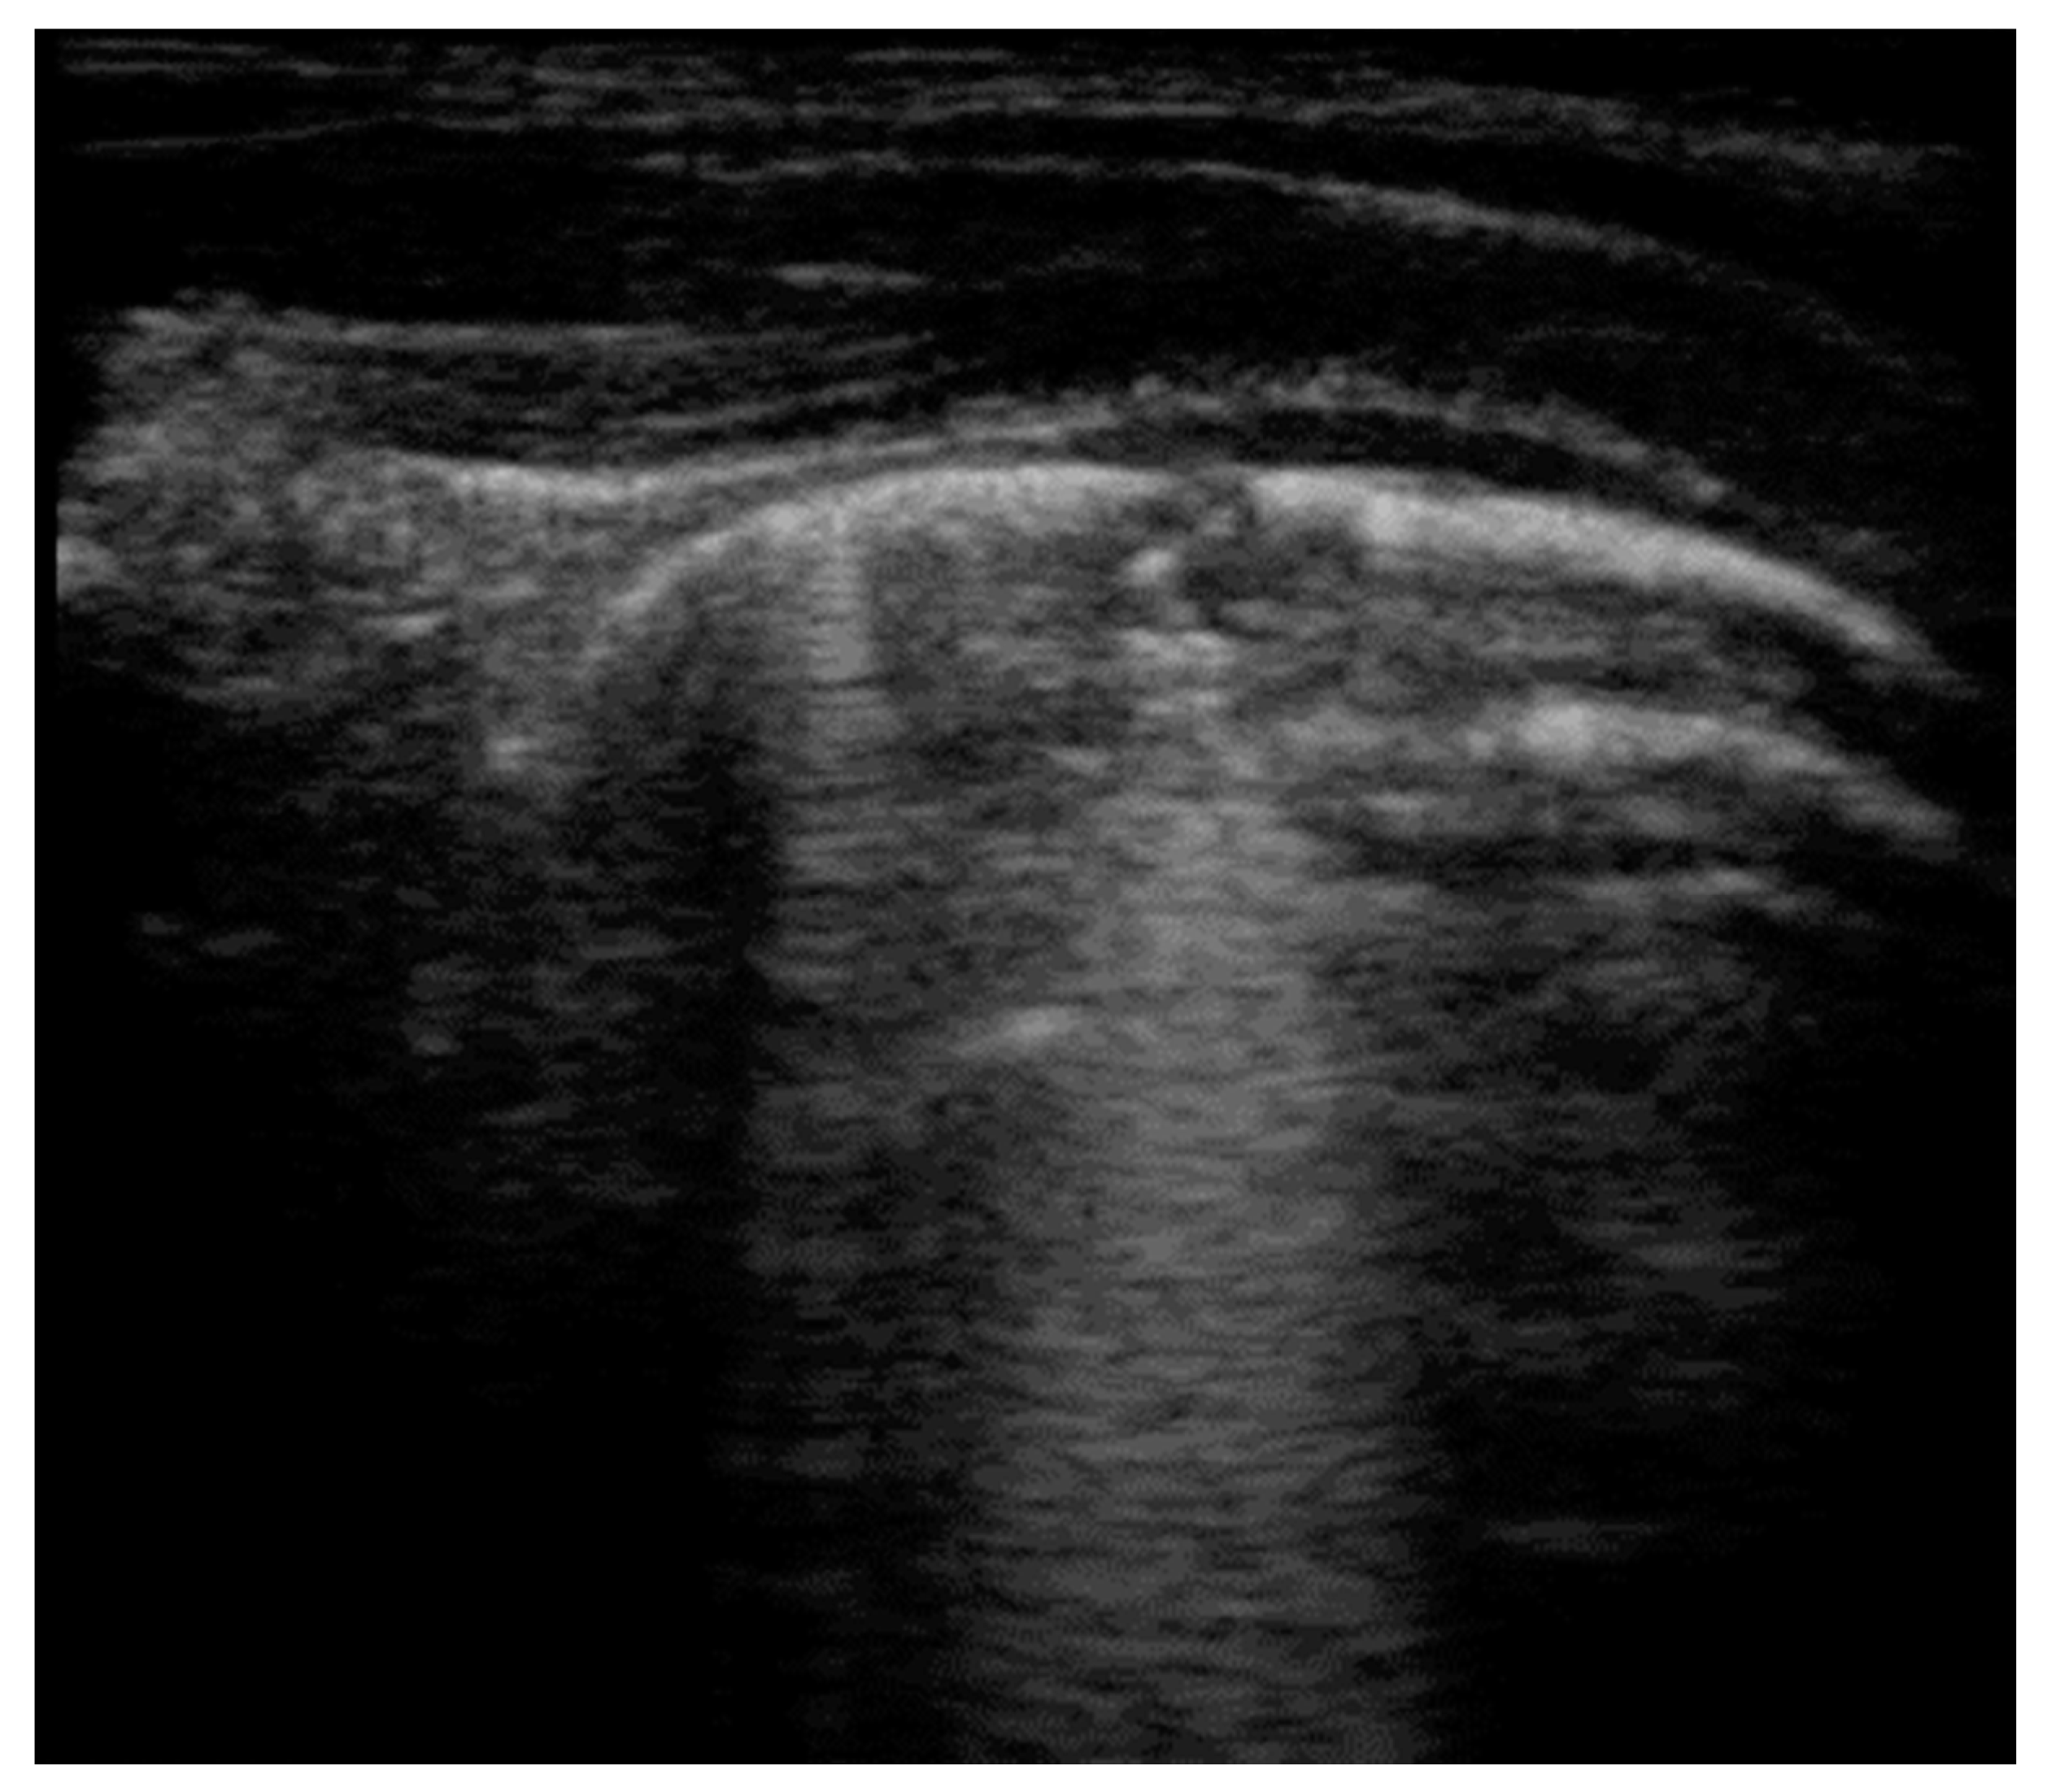

- Seashore sign (lateral): echogenic pleural line divides the image in the motionless part represented by horizontal lines (sea waves) and the part below that appear granular (sand) as the normal to-and-from motion of the lung is reflected over that area (normal lung sliding).

- Barcode sign (central): absence of a dynamic image, substituted by a static posterior acoustic shadowing (horizontal lines).